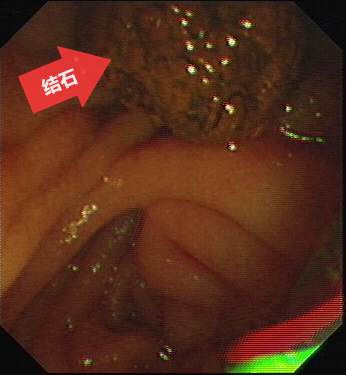

圖五:結(jié)石(箭頭所指)已取出至腸腔。

第五步:用取石網(wǎng)籃將結(jié)石從膽總管內(nèi)取出到腸腔,通過(guò)腸道排出體外。